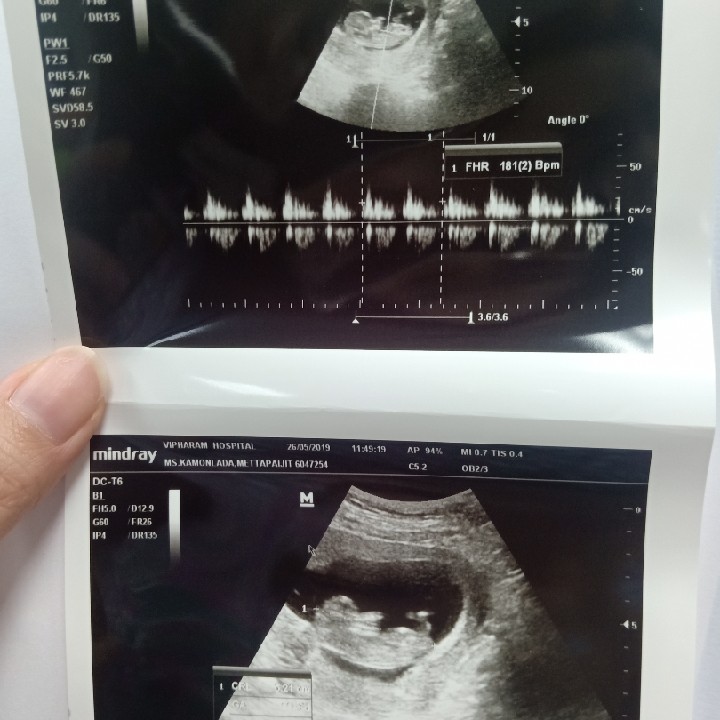

12Wค่ะ

3เดือนแล้วค่ะ..เริ่มเห็นแขน ขา บ้านใหนเหมือนกันมั๊ยค่ะ???3เดือนเห็นชัดขนาดนี้เหมือนกันรึป่าวค่ะ

,ตอน12วีคค่ะ ตอนนี้15+3ค่ะ

13week ชัดเหมือนกันจ้า

พึ่งซาวด์ตอน 14 week 6 day ค่ะ

ซาวด์ตอน17 w ค่ะชัดมากก

บ้านนี้เห็นตั้งแต่10w6d

บ้านนี้ซาวตอน12+2 คร้า